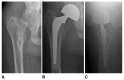

The treatment of hip fractures in the elderly represents a major public health priority and a source of ongoing debate among orthopaedic surgeons and anesthesiologists. Most of these injuries are treated with surgery in an expedient fashion. From the surgical perspective, there are certain special considerations in this population including osteoporosis, pre-existing arthritis, age, activity level, and overall health that contribute to the type of surgical fixation performed. Open reduction and internal fixation versus arthroplasty remain the two major categories of treatment. While the indications and treatment algorithms still remain controversial, the overall goal for these patients is early mobilization and prevention of morbidity and mortality. The use of preoperative, regional anesthesia has aided in this effort. The purpose of this review article is to examine the various treatment modalities for hip fractures in the elderly and discuss the most recent evidence in the face of a rapidly aging population.